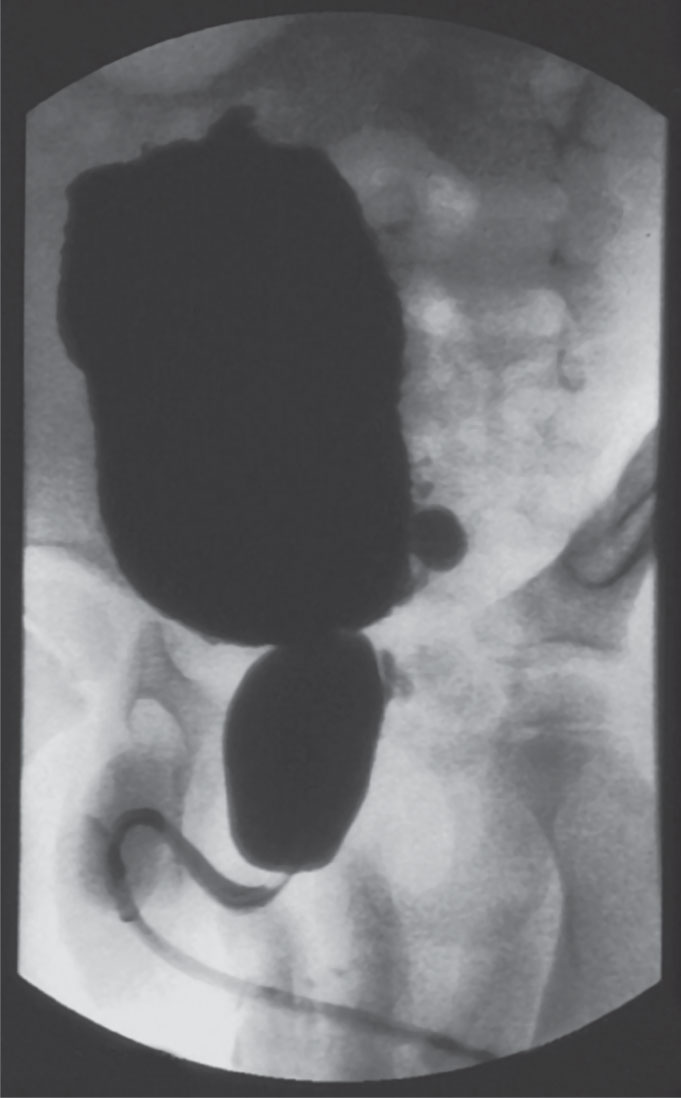

![]()  |

الشكل (10) الدراسة البولية الديناميكية بمشاركة التنظير الشعاعي.  |

-5 الدراسة الديناميكية البولية بمشاركة الأشعة videourodynamics:

تُعد قمِّة الدراسة والمِعْيار الذهبي gold standard، وتكمن أهميتها بالتنظير الشعاعي المُتكَرِّر طوال فترة الدراسة وبالأخص لعنق المثانة والإحليل الخلفي (الشكل10) (الوسيلة الوحيدة المُتاحة لتقصي وجود ارتخاء المصرة الداخلية ومدى هذا الارتخاء أو وجود خلل تآزرها مع المثانة)، إضافة إلى دراسة المصرة الخارجية دراسة دقيقة ومُوثقة في طوري الامتلاء والتبول، لتحديد شكل المثانة، ولتَحري جَزر مثاني حالبي ودرجة شِدَتِه :VU-reflux وهل هو منخفض أو مرتفع الضغط، ولتحديد السعة الفعلية للمثانة خاصة بوجود الجزر.